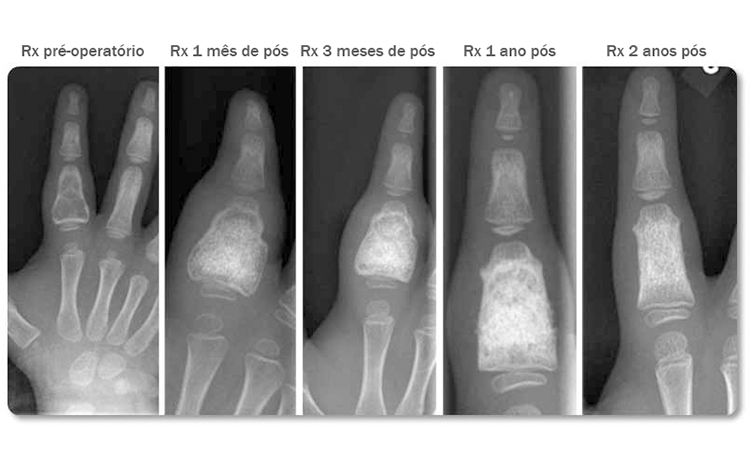

Paciente: Criança de 3 anos de idade com cisto recorrente na falange proximal do dedo indicador.

Procedimento: O tumor foi removido, e o defeito foi preenchido com 2 cc de BonAlive granules 0.5-0.8 mm e 2 pedaços de osso autógeno, de 2-3 mm.

Evolução Clínica: Foi realizado o acompanhamento do caso, 1,3,12 e 24 meses pós operatório. Aos 24 meses não foi observada cavidade e a região havia sido preenchida por osso trabecular, de forma homogênea. A falange teve crescimento em comprimento e foi remodelada quase que totalmente para o seu formato natural. O BonAlive® granules não impediu o crescimento natural do osso da criança. Tratamento de cisto ABC recorrente com vidro bioativo em criança, permite uma boa remodelação e crescimento ósseo. Lindfors N. Bone, 2009;45(2):398-400.